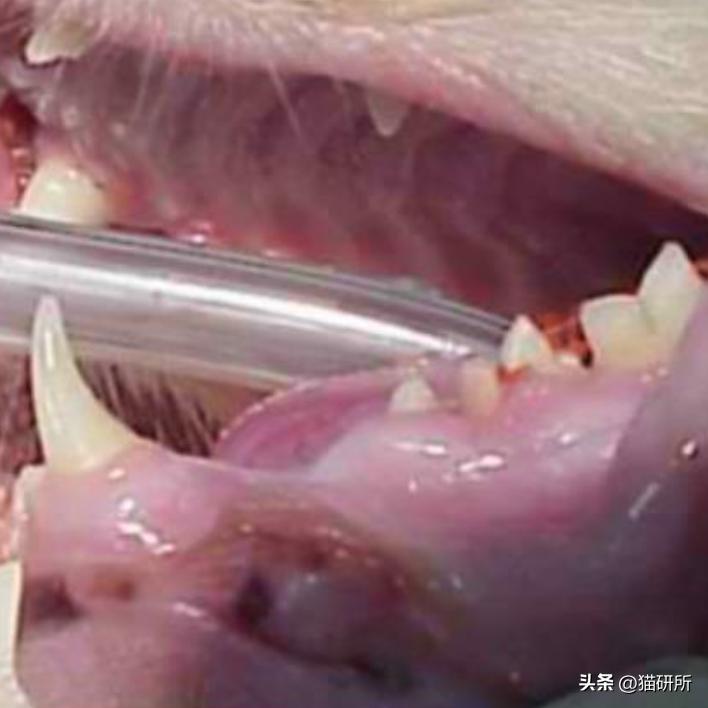

2004年,猫咪Zora因为多个乳牙未脱落,影响恒牙正常生长,被主人带到医院进行了拔牙手术。

Zora嘴里未脱落的乳牙 图自:Knees & Teeth Case Series Presentation

和Zora类似,Spaz同样由于多个乳牙滞留影响恒牙,进行了拔牙手术。

Spaz的牙齿检查结果

图自:Knees & Teeth Case Series Presentation